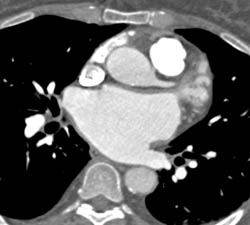

Av Nodal Branch Off the RCA